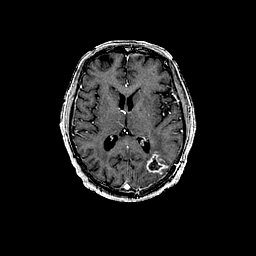

Glioma overlay -- Slice #62

[Home][Help][Clinical] Slice 62